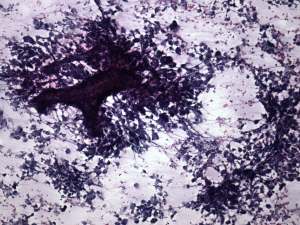

First cytological examination yielded not-diagnostic material. On a second attempt an anaplastic tumor was diagnosed with the possibility of secondary thyroid carcinoma.

We present in the cytological pictures two very rare phenomenons, single cell necrosis and mitotic figures.